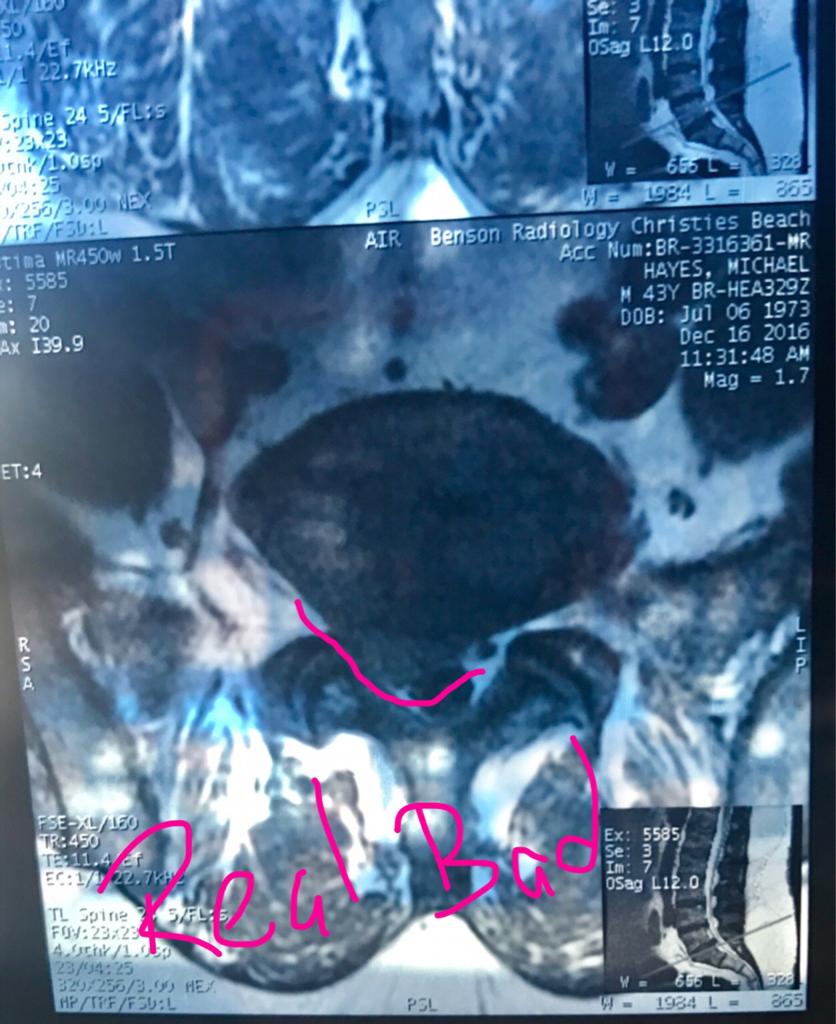

With my current herniated Disc I doubt I'll ever be riding again!!

I've been there Tombie. Believe it or not you can recover.

Having had the pain of a prolapsed disk, I can say i'ts probably the worst you will ever experience. I'm pretty much over it now and am even capable of short bursts of heavy work.